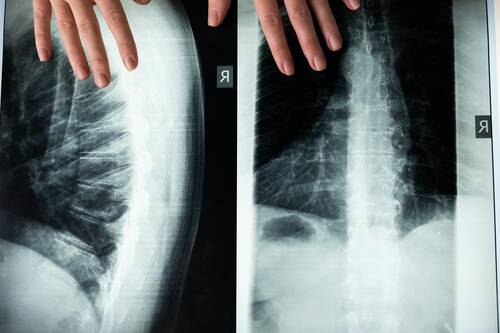

Scoliosis Surgery Before and After: What Changes?

Most people notice the differences: straighter alignment, more level hips and shoulders, and improved side-to-side balance. Many patients also report reduced pain and better tolerance for daily activities, though outcomes vary according to diagnosis and age. At the same time, scoliosis surgery won’t make the spine “perfect.” Some stiffness, occasional aches, or limited activities may persist. Continued follow-up helps doctors monitor bone healing and hardware position to facilitate the best possible outcomes.